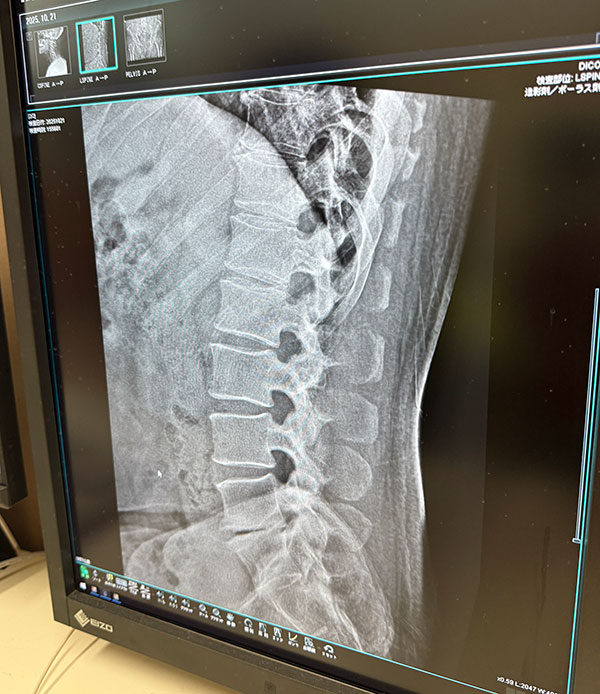

| 2025/10/21火 楓の森で検査 ↓前 次↑ 朝イチ女王送ってクルっとひさ枝へ。 ![]() 8:30ぐらいですが少し落ち着いてきたのかな。 ![]() 姉やんから頼まれたお土産うどん買いがてらでしたが久々釜玉かけを。うむ、自分にとってのこの店はやっぱこれやな。 ![]() 主治医モリケン先生のトコにも行きます。受付の美女に「いつもの膝ですか?」→「はい、それに加え腰と尻と首と。。」→「事故か何かで?」→「いや転んだと言うか。。」→「いつですか?→「10/18土です」てか 「先生も知ってますので」 ※その場にいたw というやりとりをしました!レントゲン撮ってもらいました。 ![]() ドキドキしながら結果を。 ![]() 首は一箇所狭まってるそうで、今回のが原因ではなく加齢とのこと。ヨシキよりかはマシでしょう。 ![]() ヒビ等はないようです。 ![]() 椎間板はもうすぐヘルニアかもやけど、それは元々やからなあ。 ![]() パイプ椅子で頭打ったけどそれなかったらもっとヤバかったかもとのことでした、ともかくHOTしつつ 正式に椅子アクションを禁止 ※ジャンプもデス されました。新しい面白いコトを探しましょう。 ![]() いつもの膝ヒアルロン酸デュアル打ってもらって後に。 ![]() ひさ枝でもらった麺で寄せ鍋ですか。 ![]() 土曜のライブや日曜からの九州出張までに痛さマシになってて欲しい。 ↓前 次↑ | ||